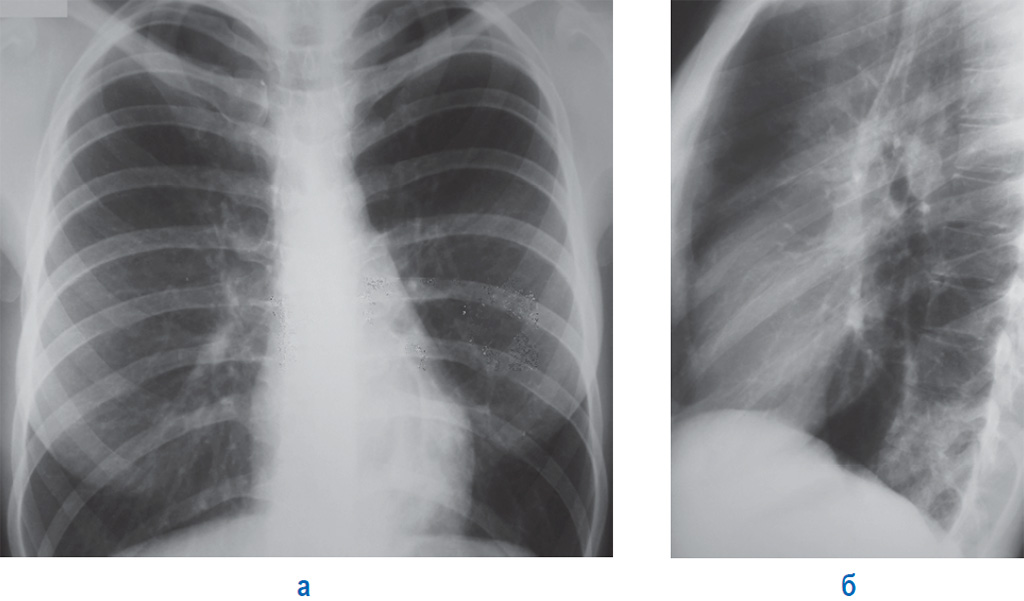

Респираторные болезни

Пневмония не всегда проявляется повышенной температурой тела и плохим самочувствием

Сильные колющие боли, возникающие при глубоком вдохе под лопаткой, могут быть следствием пневмонии, бронхита и даже тяжелой формы ОРВИ или гриппа. Если же выраженность симптомов не слишком сильная, речь может идти о плеврите. Нередко эти нарушения дополняются такими признаками:

- сильный сухой или влажный кашель;

- лихорадка, озноб, жар и высокие показатели температуры;

- тяжесть в грудной зоне.

Хроническая пневмония и бронхит не имеют таких ярких признаков и могут протекать скрытно. Однако таким нарушениям всегда предшествуют патологии респираторной системы или неблагоприятные внешние условия: чрезмерная влажность, запыленность, пребывание в городах со смогом.

- редко обходятся без рентгена грудной клетки и УЗИ брюшной полости;